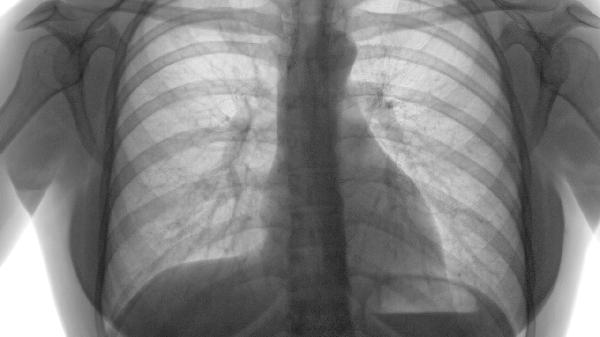

肺气肿导致脚和脸浮肿怎么处理

肺气肿引发的脚部和面部浮肿,通常是因为右心功能出现障碍,可以通过使用利尿药物、吸氧治疗、控制基础疾病、减少食盐摄入以及改善生活习惯等方式来缓解。肺源性心脏病是肺气肿发展到后期常见的并发症,主要表现包括下肢浮肿、颈部静脉明显扩张等。